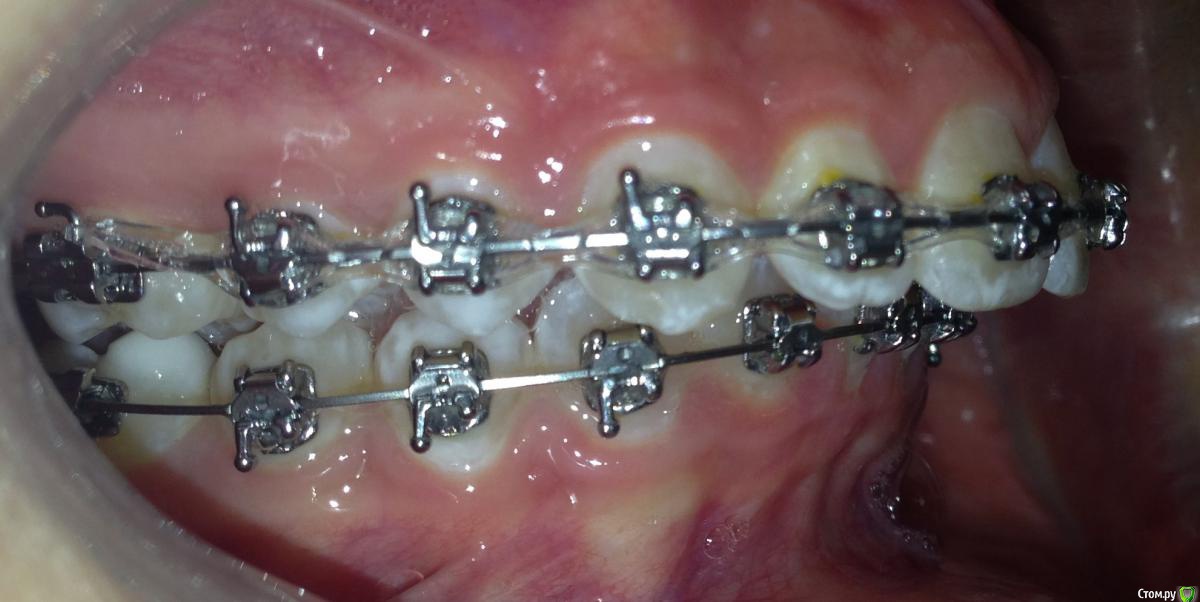

Пациентка 14 лет. Было принято решение лечить без удаления, тк. профиль не позволяет да и ретропозиция нч. Лечение идет. Я назначила ранние эластики слабые, на 17/25 нити на вч и 18 нити на нч. по 2 классу короткие 3,4-4,5. Пациентка пришла через месяц жалуется на щелканье челюсти во время ношения эластиков и сразу после их снятия. Т.е. если открывает рот, то челюсть скачкообразно двигается и щелчками. Последние 2 недели, когда много говорит, то вообще стала заедать. Это она так сказала. После отмены эластиков (страшно), через неделю пришла, рот открывает ровно, без девиации, щелчков нет. Вопрос: почему щелкает и что с этим делать? По поводу прикуса, посоветуйте, пожалуйста, как нормализовать? Аппарат типа гербста? может ей твинблок сделать? Эластики? К сожалению другими методами я пока что не владею. Спасибо, очень жду ваших советов.